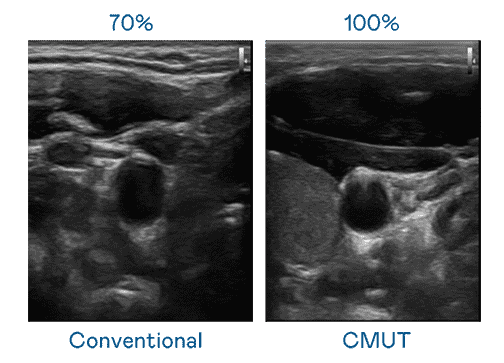

CMUT 技术是一种用电容式微机电元件来产生超音波讯号的技术。。与传统 PZT 压电式技术相比,,,,CMUT 频宽增加 30%,,更宽频的超音波讯号让影像解析度大幅提升,,,,是实现高影像品质医疗超音波扫描、、、促进精准医疗发展的关键技术。。。。

超音波影像的解析度高低,,,,首先取决于探头能发出的讯号频宽。。NG大舞台 CMUT 可提供高清晰的超音波讯号,,提供高频宽、、、、高灵敏度、、、影像纹理细节更高的超音波影像,,,,协助医护人员缩短影像判读时间及利用精准的医疗影像进行诊断。。